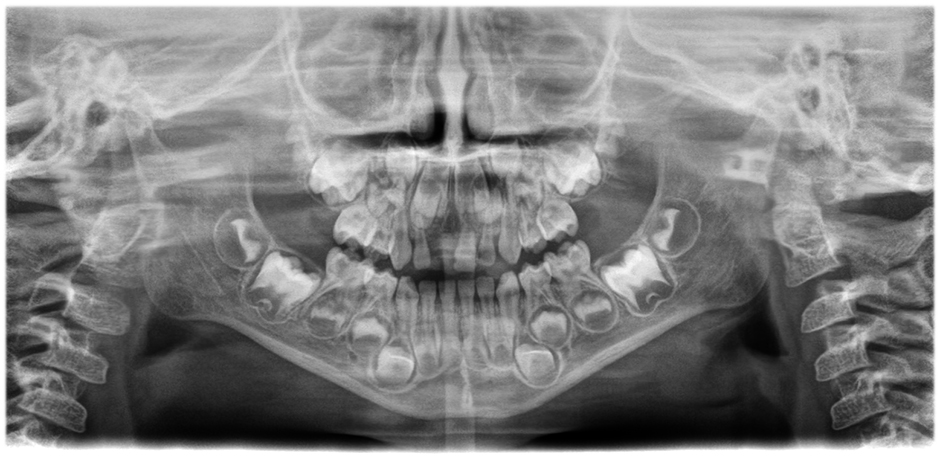

• Imágenes panorámicas de nitidez y definición extraordinarias

gracias al innovador sistema de enfoque automático de 21 capas integrado a la perfección con la corrección de posición del paciente.

Mueva el botón deslizante para ver la diferencia (a la izquierda, imagen sin enfoque automático; a la derecha, con enfoque automático y posición corregida del paciente).